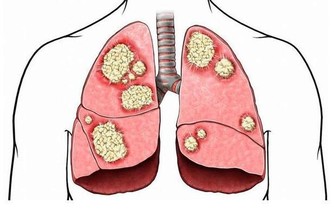

身邊受痛風困擾的朋友越來越多,這種常發生在中老年人身上的疾病,如今在20幾歲的年輕人身上竟也經常發生了,好可怕,防痛風,你我都要知道一點...... 痛風:是一種因長期嘌呤代謝紊亂,血尿酸增高而引起的疾病,是我國中老年人較常見的代謝性疾病。臨床表現急性關節炎反復發作,痛風結石形成,關節畸形,痛風性腎病,甚至腎功能衰竭。

其實這也是腎虛的一種症狀,因為腎的過濾功能減弱了,血液裡的酸毒排不出去,隨著血液循環流動。大腳趾關節是人體的最末梢關節,酸毒的結晶體最容易積 聚在這裡,也有的人是大拇指關節痛,都是同樣的道理。如果你不去調整腎臟,恢復它的過濾功能,酸毒結晶長期擠壓關節,最後關節不能正常活動,出現變形了。所以痛風患者不僅要改變飲食習慣,更關鍵在於恢復腎臟的機能,提高過濾能力,把酸毒排出體外才不會再複發。

痛風,是由於體內嘌呤代謝紊亂所引起的一類疾病。因其起病急驟,來勢如風,疼痛劇烈,多伴紅腫,走時較快,不留影蹤,故名痛風。該病的臨床特點是高尿酸血症,及由此引起的痛風性急性關節炎反復發作、痛風石沉積、痛風石性慢性關節炎和關節畸形。常累及腎臟引起慢性間質性腎炎和尿酸性腎結石,並引起腎功能損害,累及血管可以引起高血壓,累及心臟可以引起冠心病,並且常常伴發高脂血症、糖尿病等疾病。

因此,儘管痛風多表現在關節引起關節炎,但實際上它是一種全身病變,可引起多髒器損害,甚至危及生命,因此,必須引起高度重視。